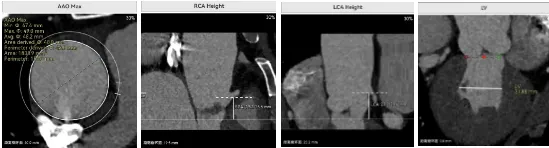

病例概览

患者病史 体检发现心脏瓣膜病半月余,平素无症状 ,有高血压病史。 后来院复查诊断为:主动脉瓣狭窄(重度)、先天性主动脉瓣二叶瓣畸形、心室肥厚、升主动脉扩张心功能 I 级(NYHA 分级)、高血压病 2 级(极高危)。 术前 CT:Type0型二叶瓣,瓣叶增厚,无钙化,类风湿性;瓣环径25.6mm,LVOT稍收窄,瓣环水平夹角66.6°,轻微横位心;左右冠开口高度可,瓣叶不长,无冠脉风险;心室收缩末内径约32mm,室壁增厚;外周入路无明显迂曲,无钙化、双侧内径可、双股中分叉,右侧为主入路能够支持20F大鞘通过。 造影角度及入路:LAO 6° CAU 13° 手术策略 采用右侧股动脉为主入路,左侧为辅助入路,常规穿刺。推荐使用20球囊预扩,预装TAV29瓣膜,初始定位对齐瓣环上0mm开始释放。 手术过程 20号球囊预扩无明显腰征 输送器过弓跨瓣顺滑 80%工作位观察 术后造影,瓣膜释放位置良好,无瓣周漏 术后超声:人工生物瓣释放后形态满意,瓣叶开放、关闭活动良好,无瓣周漏;跨瓣血流速度降至 2.5m/s,平均压力梯度6mmHg,符合手术预期。 Prostyle A®预装干瓣——“刚柔并济”助力临床最优化解决方案: 丝滑过弓能力:Prostyle A®短瓣架设计联合远端超滑亲水涂层,即使没有联合使用snare,都可以柔顺过弓,该例横位心的患者更好的展现了输送系统的柔顺性; 平衡的径向支撑力:该例患者Type0型二叶瓣,术后形态展开良好且无瓣周漏,在横位心等复杂情况下实现稳定锚定。 80%可回收设计:80%工作位观察,起搏时间更短,对患者损伤减少到最小,也利于术中精准调整瓣膜位置,保证术后效果。